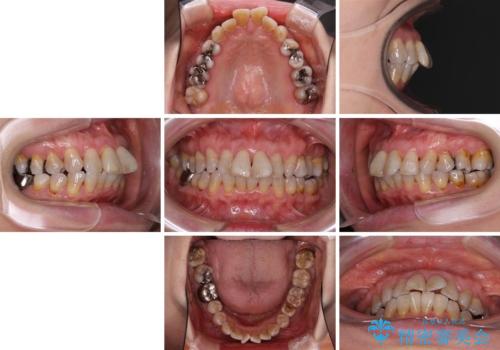

- 突出した口元を引っ込めることを希望して来院された患者様です。

上下左右第一小臼歯4本を抜歯して、口元を改善するワイヤー矯正を行うこととしました。

長年気にされていた口元の突出感が改善されたため、もっと若い時分に矯正をすればよかったと思われていました。